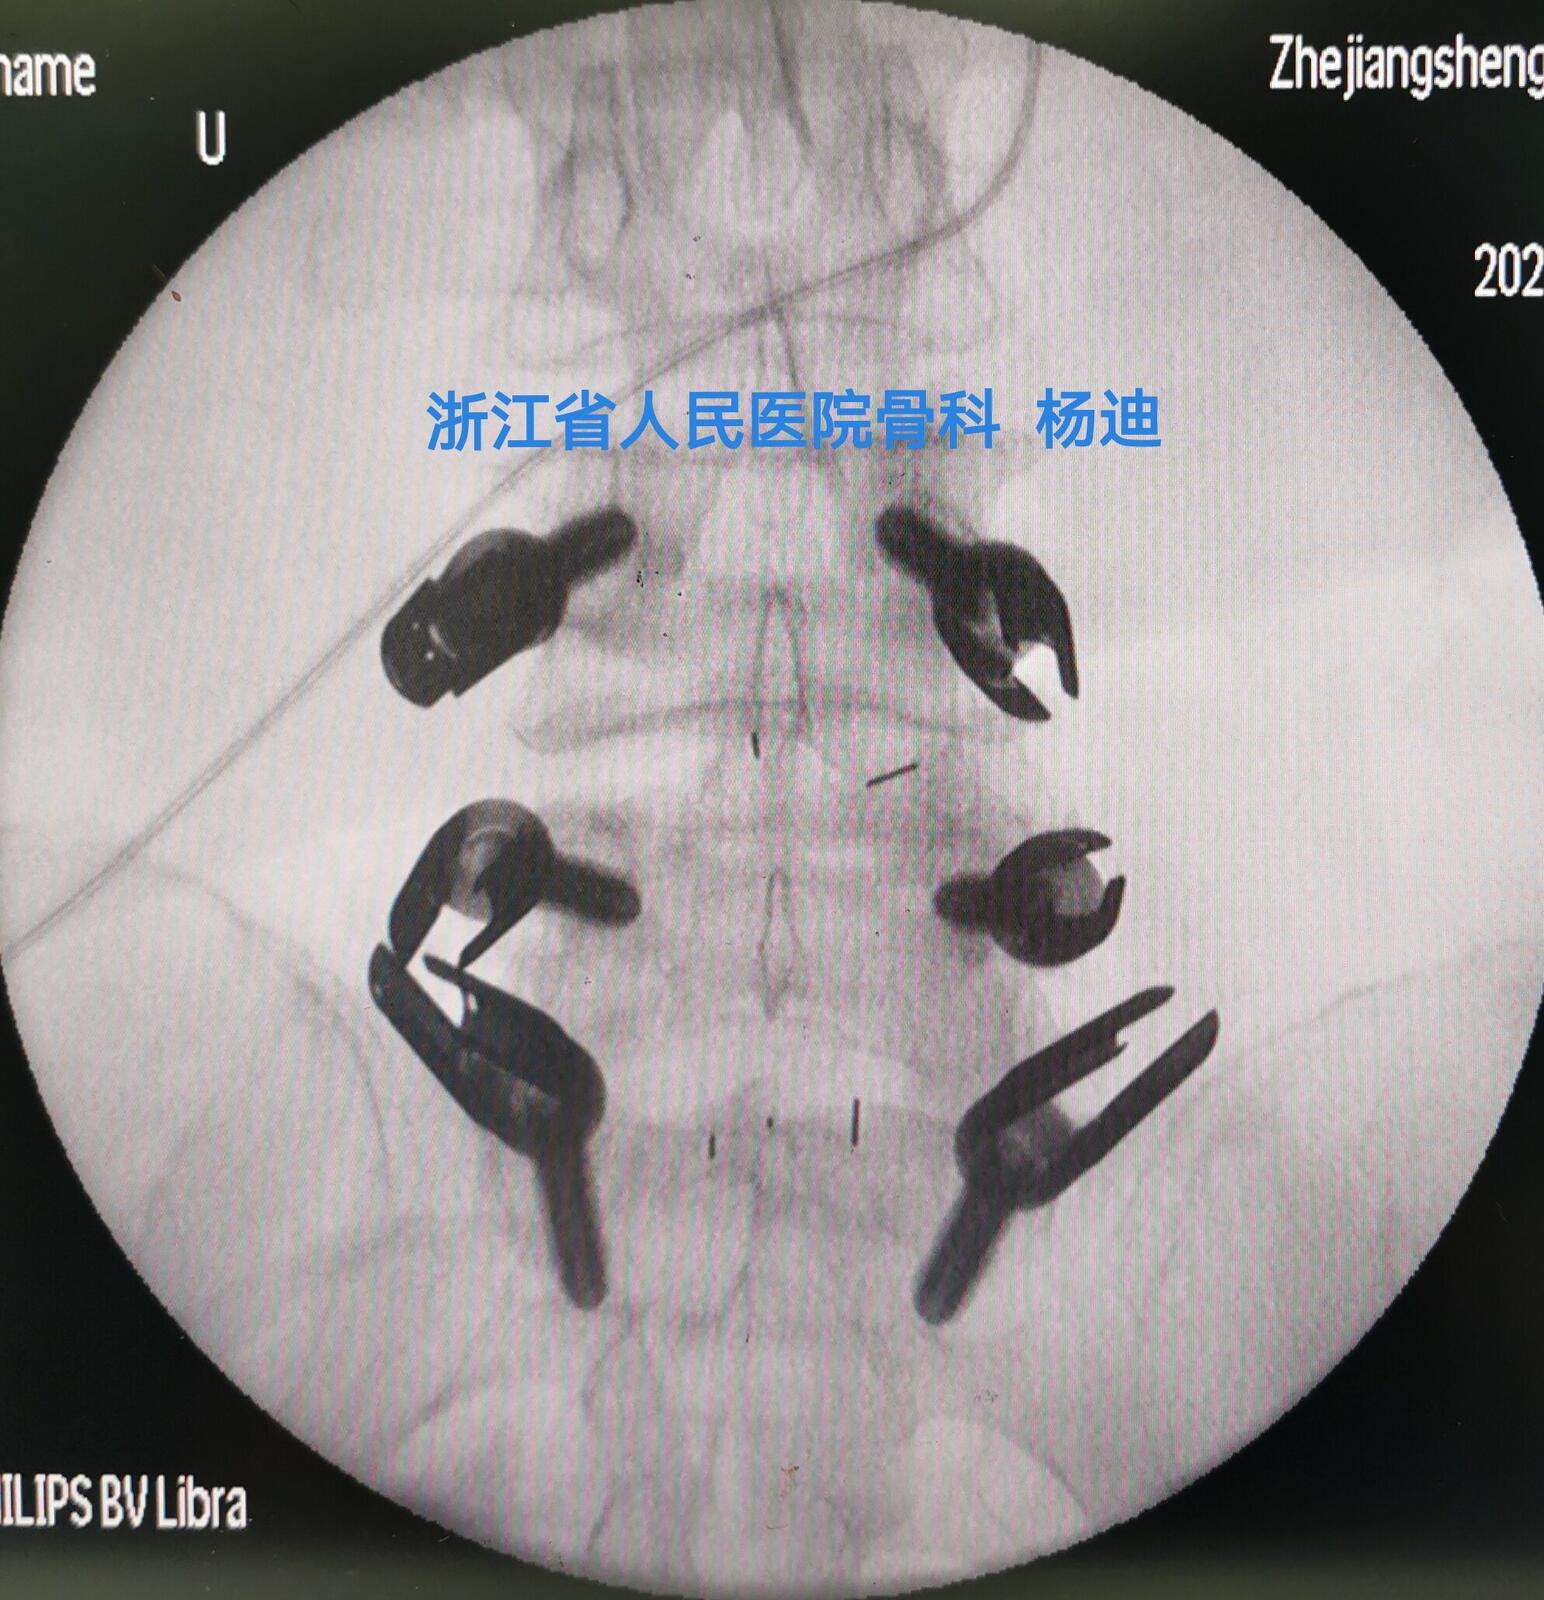

图为腰4/5、腰5/骶1减压椎间融合器置入、经皮螺钉置入后,C臂透视见融合器及螺钉位置、长度满意。

图为腰4/5、腰5/骶1减压椎间融合器置入、经皮螺钉置入后,C臂透视见融合器及螺钉位置、长度满意。